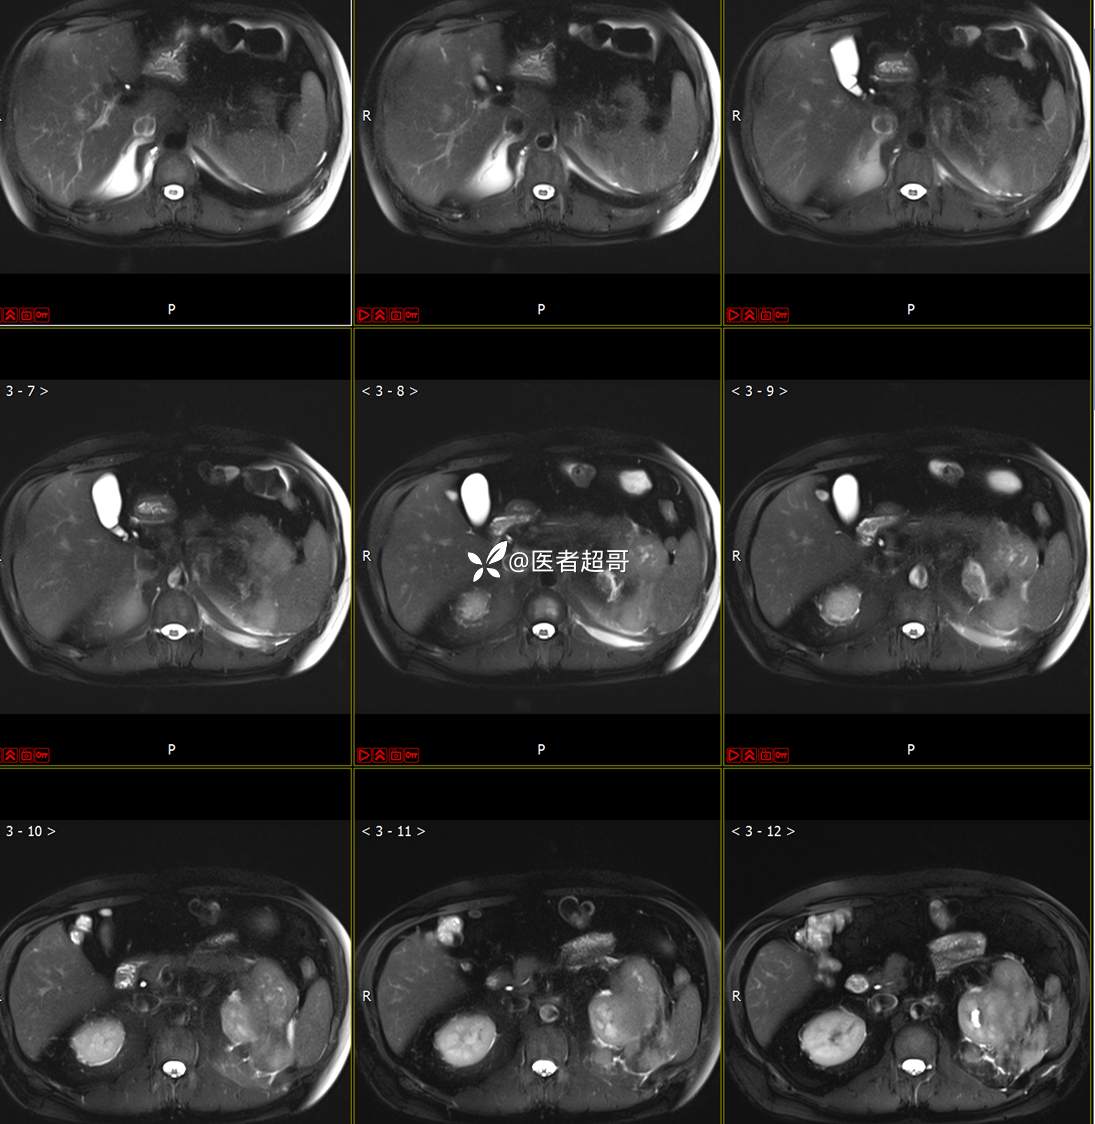

主 诉:查体发现左肾肿物9天。

现病史:患者9天前于附属医院行常规腹部CT检查时,发现左肾占位性病变并肾周脂间隙软组织增多,自述无明显腰腹部不适,无尿频、尿急、尿痛及肉眼血尿,未予特殊治疗,患者近期无头晕头迷,胸闷气急,腹胀腹泻及其他部位明显不适,遂至我院就诊,门诊以“肾肿物”收入院,患者自发病以来,精神可,睡眠饮食可,大便正常,体重无明显减轻。